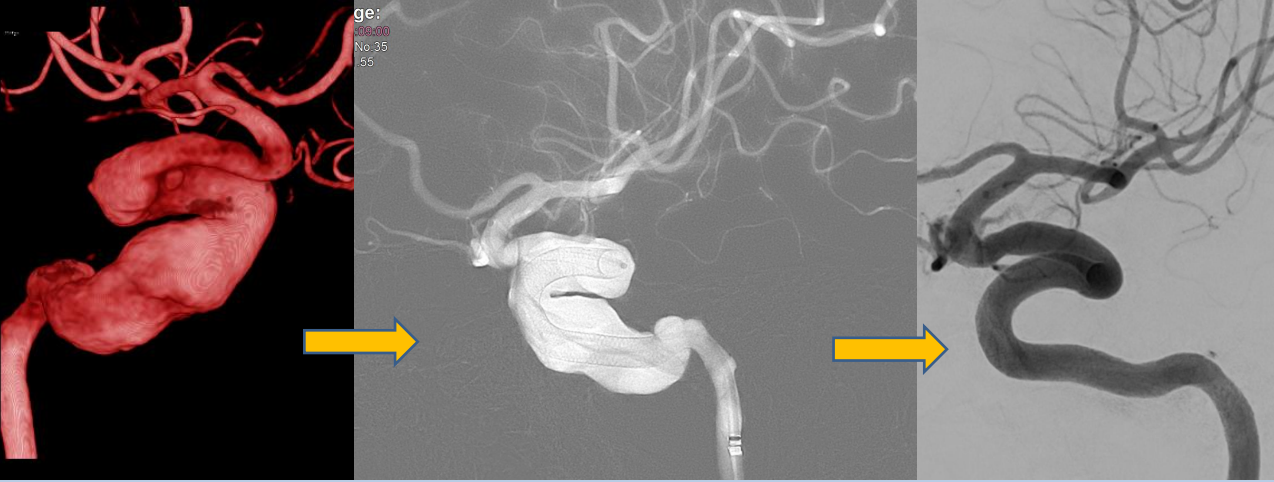

Wir sind spezialisiert auf die minimal-invasive, endovaskuläre Behandlung zerebraler und spinaler Gefäßfehlbildungen und Gefäßverschlüsse. Dazu gehören insbesondere komplexe Aneurysmen, arteriovenöse Fehlbildungen und Fisteln, sowie die akute und präventive Behandlung des ischämischen Schlaganfalls.